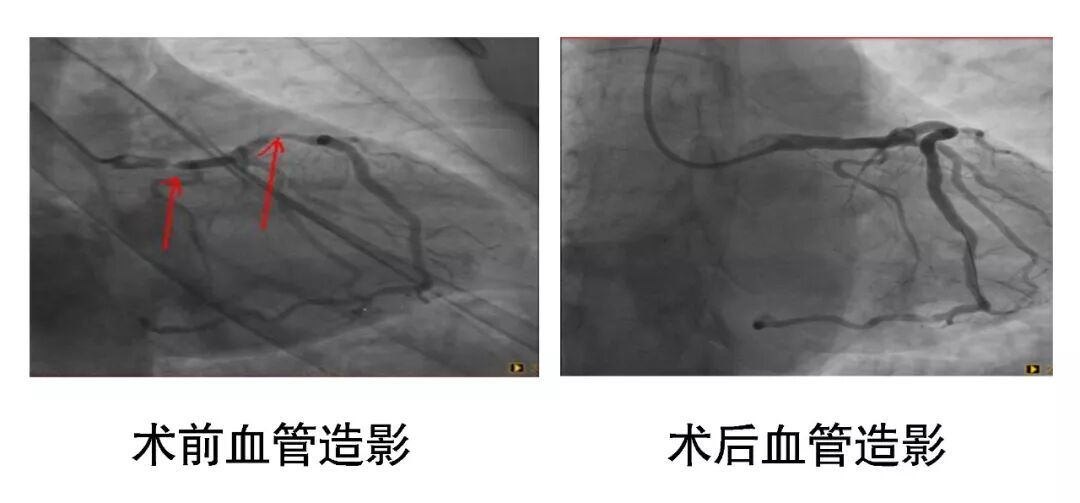

近日,桓台县人民医院心内科一病区介入团队成功为两例心脏冠脉左主干严重狭窄患者实施介入支架置入手术。

两例患者因胸闷胸痛在外院治疗效果不佳,转入我院就诊。造影结果显示两例患者均为左主干严重病变。其中一例患者,因先天性右冠脉、回旋支发育短小,所以左主干供血范围巨大,一旦左主干发生病变,将危急生命。另一例患者左主干完全闭塞!患者能自主来院已经是个奇迹了。两例患者随时有生命危险,必须立刻进行手术治疗! 在和患者及家属充分沟通后,王磊主任带领心内科一病区介入团队分别为两例患者实施介入支架置入手术,开通了闭塞血管,患者胸痛症状当即缓解,转危为安。 病例一 病例二 据王磊主任介绍,心脏冠脉左主干是心脏供血的“总闸门”,一旦发病,多数表现为猝死,死亡率高达80%以上。一旦出现胸痛症状,切勿大意,应及时就医以便早发现早治疗。